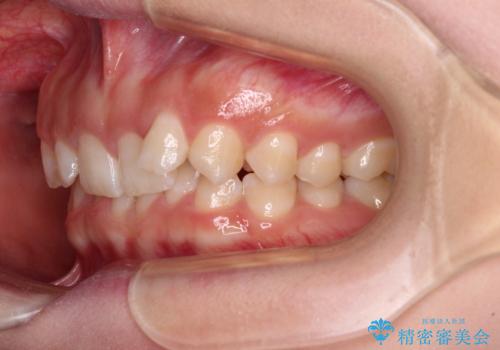

- 前歯のデコボコとディープバイトを気にして来院された患者様です。

左上前歯前方に飛び出しているため、歯列全体が前方に移動している状態でした。

短期間で確実に仕上げたいとのことで、アンカースクリューと補助装置を併用して歯列の後方移動を図り、ワイヤー装置にて矯正治療を行うこととしました。